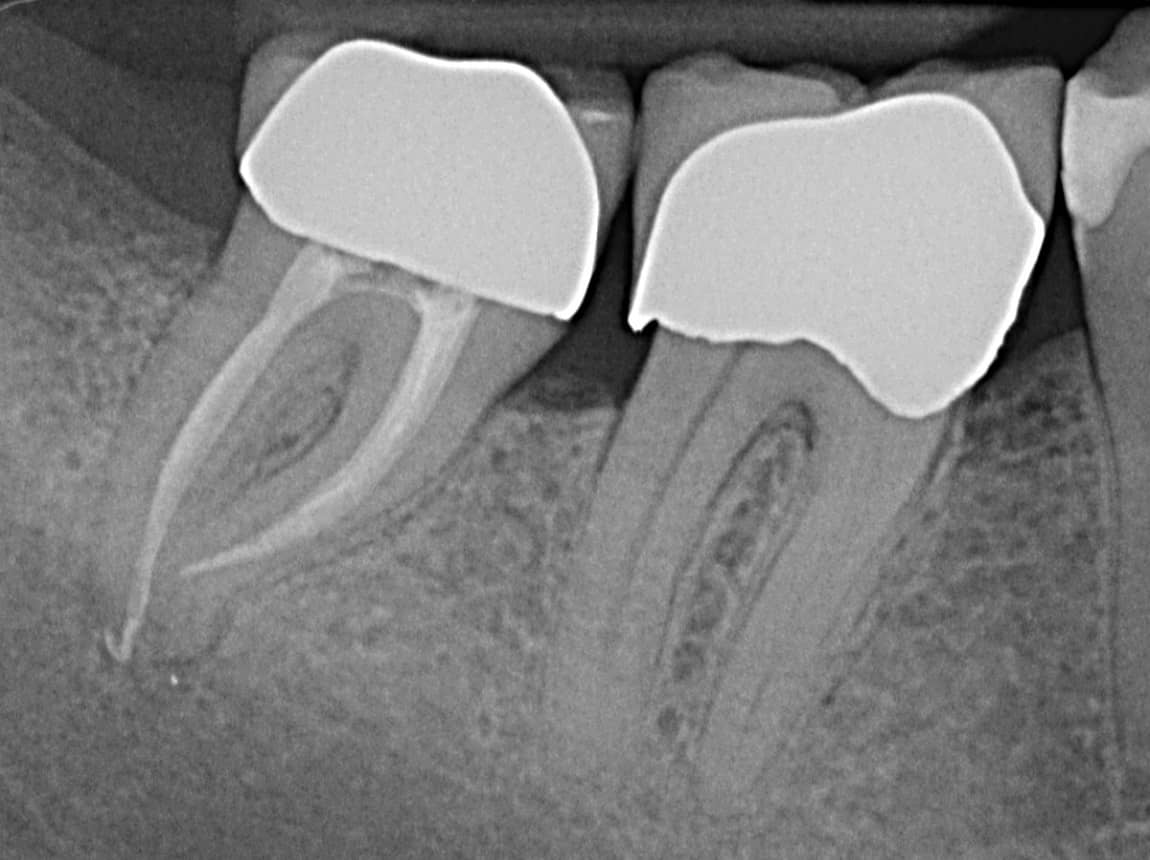

Ist der Defekt zu tief oder der Nerv im Zahn abgestorben, ist vorher eine Wurzelkanalbehandlung notwendig. Dabei wird der Hohlraum im Zahn gesäubert, desinfiziert und anschließend mit Guttapercha versiegelt. Das Ganze erfolgt in unserer Praxis in der Regel mittels moderner maschineller Aufbereitung und durch suffiziente Lokalanästhesie können unnötige Schmerzen verhindert werden.